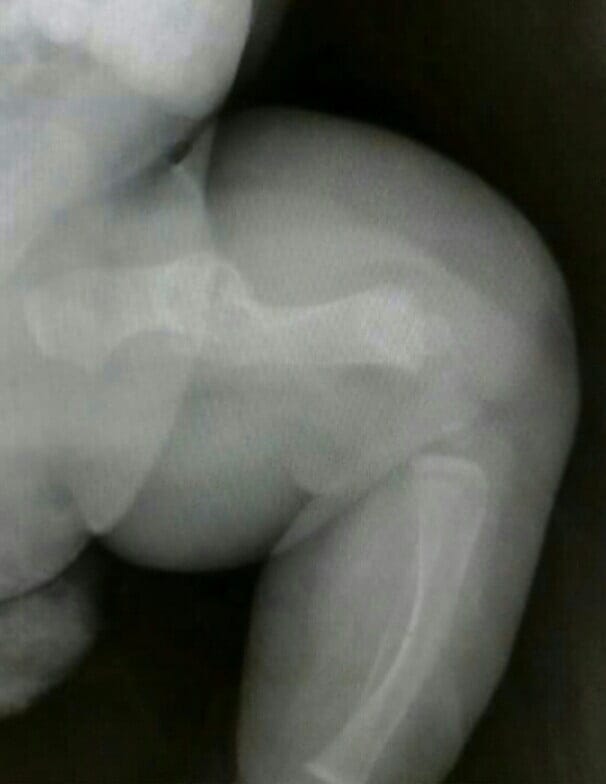

Olaya sigue con el ciclo de Pamidronato, ya lleva su cuarta sesión y los resultados positivos son visibles. La madre de Olaya, Laura Goberna, se ha mostrado muy satisfecha tras la observación de las radiografías, donde se puede apreciar la pérdida de parte de la curvatura de los huesos.